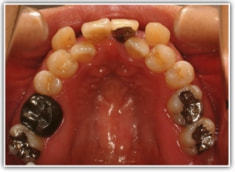

治療開始時

治療開始から約1年後

セファロ分析結果:上顎の劣成長と下顎の過成長が認められる値が出ています。重度の叢生といえます。

顔面の幅径はかなり狭い傾向にあります。